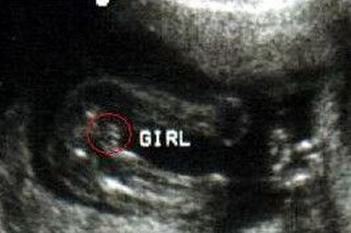

判断是女孩主要通过B超看胎儿的两腿之间是否有三条线。需要注意的是,只有一些经验比较丰富的妇科医生才能分辨出来,一般就是通过B超检查的图像,看胎儿有没有相应的性器官特征,而女孩比较常见的就是三条线,而男孩就是有凸起,正是因为这两个比较明显的特征,让很多孕妇都猜准了孩子的性别,能够早做准备。

1. 两边短中间长:通过B超图像能最清楚的分辨是女孩的特征就是两边短中间长的三条线,这个是非常明显的三线特征了,也是比较常见的一种形状。

2. 三条线不一样长:很有可能因为照射角度的问题,所以很多时候并没有看到很清楚的两短一长,在发现三条线不一样长的时候其实也有可能是女孩,只是因为角度影响了视角。

3. 三条线中间有亮点:这个也是比较容易让人认错的一个东西,因为大家都默认的有亮点的就是男孩,但是这种情况下也是有可能是女孩的。